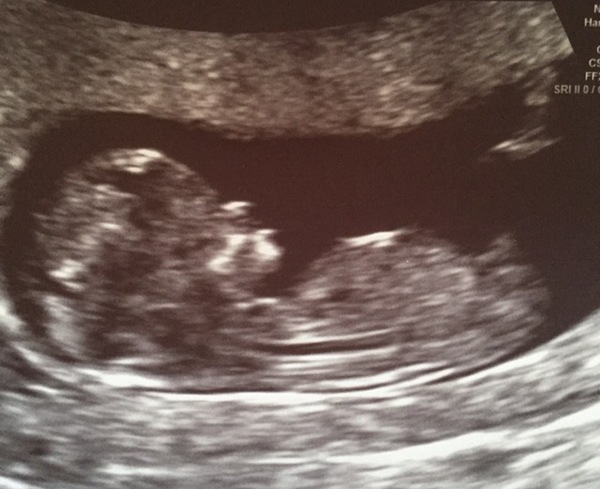

naranciata · 30/09/2016 14:34

A real baby looking thing! So exciting!

Vomited in an empty Starbucks cup on the way here, but let's skip over that for the moment.

Another scan for the day. Baby Prive is a bit of a wriggler so it look a while for a decent picture. Also altering my due date to 18th April

Lovely scan pics prive and naranciata

Great scan pics!

Excellent pictures prive and naranciata!

Hello ladies! Just checking in with a lovely 12 week scan here!

Puggleface great scan picture!